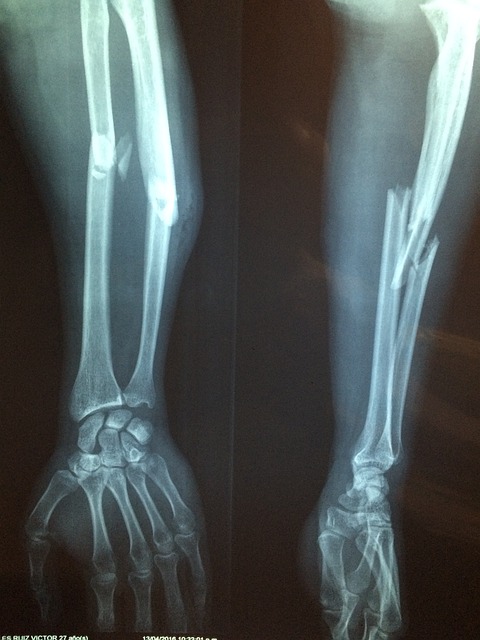

뼈에 금이 가거나 골절을 당했을 때 뼈에 좋은 음식에 뭐가 있는지 궁금해지는데요. 흔히 사골을 끓여서 우러낸 곰탕을 먹으면 뼈에 좋다는 말을 많이 합니다. 예전부터 집안에 골절 환자가 있으면 어머니가 곰탕을 한 냄비 끓이시는 모습을 많이 보곤 했지요. 하지만 소뼈를 끓인 곰탕에는 칼슘만이 아니라 인도 많이 들어 있는데, 인산이 칼슘 흡수를 억제해서 생각처럼 뼈 건강에 도움이 되는 것은 아니라는 이야기도 있습니다.